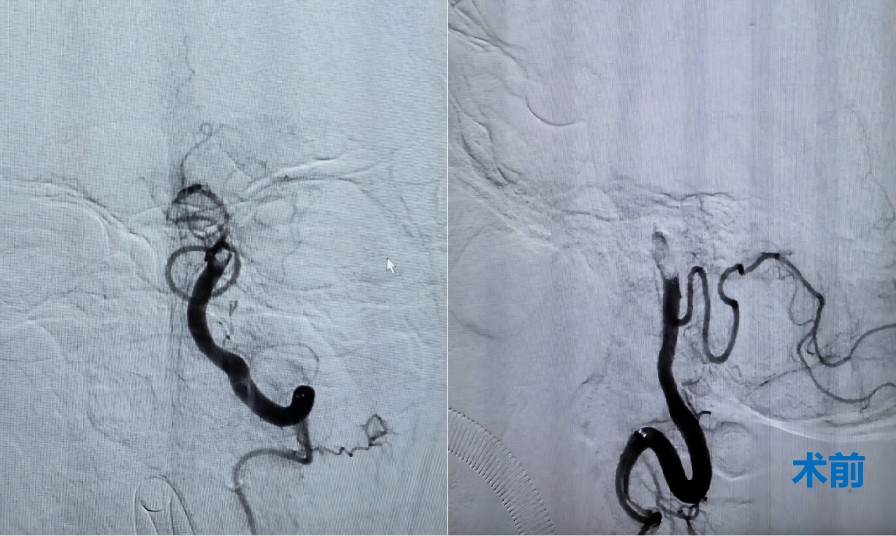

时间就是大脑,救治必须争分夺秒。神经内科医护人员高度重视,立即启动绿色通道,为患者进行紧急救治。住院总医师樊京京迅速组织完善术前准备,副主任张茹、医生范松华、进修医生朱博急诊行脑血管造影,明确患者一侧椎动脉闭塞,另一侧椎动脉线样狭窄,基底动脉未显影。

后循环梗死,九死一生,预后差,空气顿时紧张了起来。患者逐渐出现烦躁不安,提示病情在进一步加重。这种情况,必须有麻醉医生保驾护航,李喆医生火速赶来。征得家属知情同意后全麻下行椎动脉+基底动脉取栓术。在紧张有序的操作下,患者血管成功再通。经过数天的规范治疗,患者完全恢复正常,春节假期期间顺利出院。